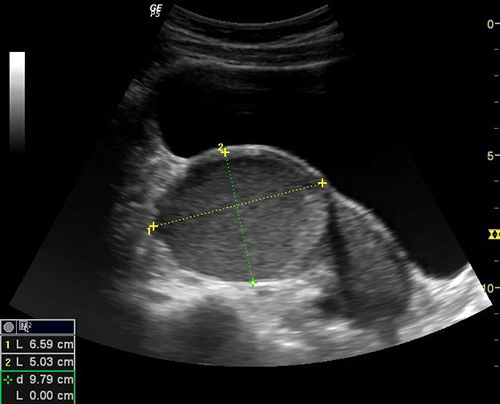

QUIZ: These images show some changes in the placenta of a 34-week pregnancy. Are they anything to worry about?